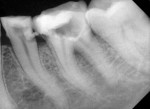

Clinical examination revealed the presence of gingival tissue through the access opening at the mandibular left first molar that occurred at a private clinic (Figure 1). Upon radiographic examination, the mandibular left first molar showed a perforation on the distolingual aspect of the pulpal floor. Proximal caries was also present in the adjacent premolar (Figure 2).

After administration of local anesthesia, under rubber dam isolation, the access opening was modified and canals were located. With the use of an apex locator (Root ZX, J Morita, morita.com)working length was established 1 mm short of the radiographic apex and was confirmed with the aid of a radiograph (Figure 3).